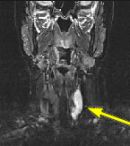

Fig.1 Fig.2 Fig.3 Fig.4

FINDINGS: The ultrasound (not shown) revealed a large solid mass behind the left lobe of the thyroid. Fig. 1-2 are MRI images of the neck demonstrating a mass behind the left thyroid lobe with hyperintensity on T2 weighted and STIR images (Fig. 1, 2 top) and enhancement higher than the thyroid (Fig. 2 bottom). Fig. 3-4 are Sestamibi images with Fig. 3 being coronal (top) and axial (bottom) SPECT images and Fig. 4 the early and delayed static images demonstrating persistent activity in the mass on delayed images while the thyroid activity washes out (arrows).

ABNORMAL SCAN: A parathyroid adenoma also demonstrates rapid uptake on the initial images. However, unlike a normal thyroid, the adenoma demonstrates persistent uptake of Sestamibi and is readily visible on delayed images. Ectopic adenomas in the mediastinum are also easily detected with this technique.